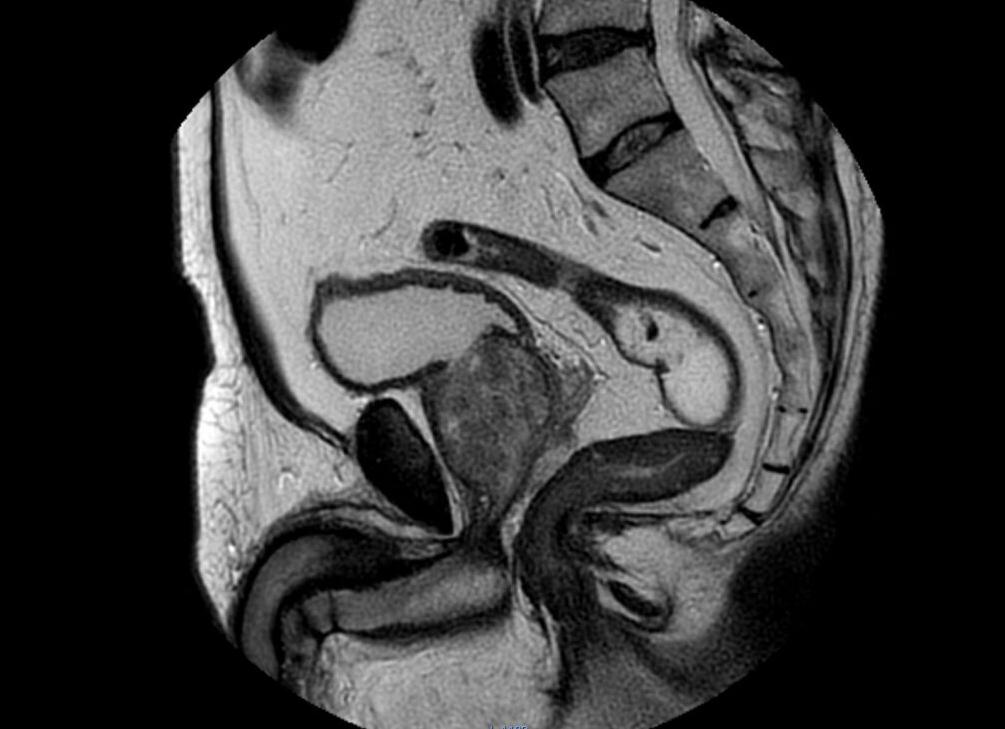

Мрт таза у мужчин

МРТ малого таза у мужчин: выявление труднораспознаваемых заболеваний

МРТ органов малого таза у мужчин в своем развитии всего за два десятка лет вышло на лидирующие позиции в области диагностирования трудно распознаваемых мужских заболеваний. Особенно следует отметить среди них те, для которых характерно слишком позднее проявление типичной симптоматики. Заболевания, относящиеся к патологиям органов малого таза, легко распознаются при помощи технологии МРТ.